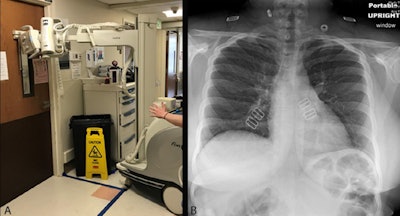

The TG-CXR method involves having only one technologist don PPE and enter the isolation room to position the patient and cassette/detector. A second technologist stays with the portable x-ray machine outside of the isolation room. Once the patient is in a satisfactory position, the first technologist provides breathing instructions to the patient and then signals the second technologist to trigger the exposure. While the first technologist waits in the isolation room, the second confirms that the acquired image is of satisfactory quality.

Importantly, since the portable radiography machine was never in the patient's room, it does not require cleaning, the authors noted.